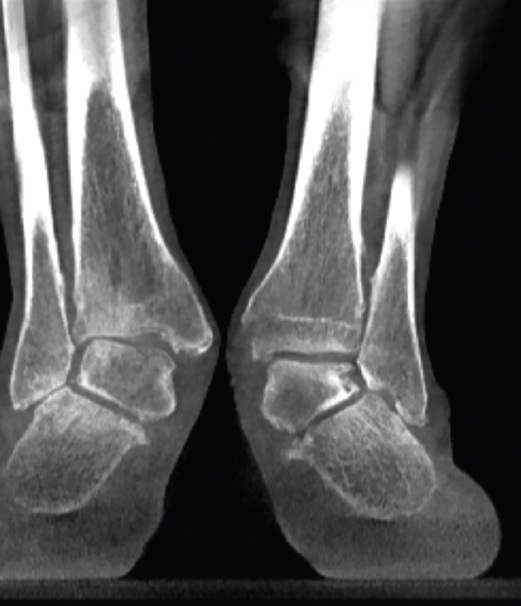

Figura 2. Severo pie plano valgo bilateral con pinzamiento fibular.

- Pie plano valgo del adulto. Permite la valoración de la articulación subtalar, el valgo del retropié y la inestabilidad de la columna medial (Figuras 2 y 3).